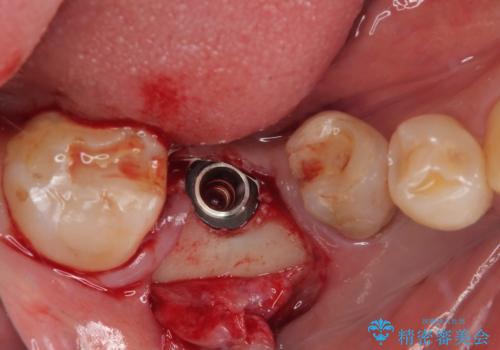

インプラント埋入時に植立具合の安定性を測定したところ、十分な数値が得られたため、速やかに仮歯を装着して咬合回復をさせることができました。

外科処置を1回に抑えることができ、あっという間に治療を終えることができました。